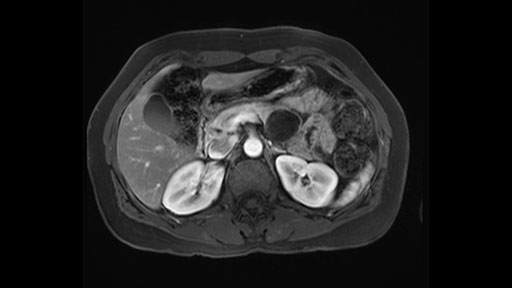

So first step that we do: mobilize the splenic flexure first to visualize Gerota’s fascia and that would help bring down the colon and expose the pancreatic tail. So now that the pancreas is visible, division of the gastrocolic ligament will come into view. And a window can be created at the inferior edge of the pancreas to slowly lift the inferior edge to expose the splenic vein behind. This is the slow-down moment that I am talking about because the MR shows that there could be contact with the cyst. It’s important to know that to avoid perforation, to avoid rupture of the cyst, because we need to avoid touching the cyst, it is quite a size of 4.3 about 4cm.

So what I would normally do in these patients, I would look at the abutment of any other organs, one, which is here, potentially the adrenal gland and two the small bowel. And two, look at the distance from the vessels which I would normally do in a coronal view. So you can easily measure the distance and third I look at the insertion of the inferior mesenteric vein. Now we can probably also see that on here. Although it's better on a CT scan and it's better on a coronal view, you want to know where the inferior mesenteric vein comes into either the splenic or the SMV, because that is typically a very important slow down moment when you mobilize the lower portion of the pancreas knowing where the inferior mesenteric vein comes in either the splenic vein or the SMV. So those are I think the three most important points for the CT scan.

If you hang the pancreas then you move down towards the right side of the patient. You know your first slowing down moment is where the inferior mesenteric vein comes in the splenic vein or into the superior mesenteric vein, you have looked at that at the scan, so you know where to expect it. You can do two things in a procedure where you can preserve the splenic vein, you can preserve the IMV as well. But in this case where you want to do an oncologic resection with splenectomy, you will transect the inferior mesenteric vein.